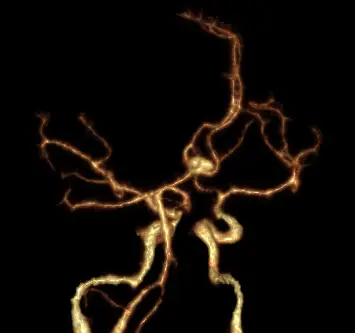

有關附圖之電腦斷層血管攝影影像,下列敘述何者正確?

顱內動脈瘤(intracranial aneurysm)最常見於 Willis 動脈環的分叉處,尤以前循環的 anterior communicating artery (ACom)、posterior communicating artery (PCom) 以及 middle cerebral artery (MCA) bifurcation 為好發位置。電腦斷層血管攝影(CTA)可在一次掃描中重建 3D 影像,迅速顯示動脈瘤之確切位置與與鄰近分枝的關係,為臨床常用的初步評估工具。

影像為 3D-CTA volume-rendered 圖,觀察可見:

- 兩側 internal carotid artery 於顱底向上分出 A1、M1 段形成 Willis 環。

- 兩條 A1 segment 於正中前方會合處可見一圓形囊狀向前上方突起,頸部位於左右前交通處,符合典型 anterior communicating artery saccular aneurysm 影像特徵。

- Aneurysmal sac 表面光滑,無明顯 daughter sac 或“blister”樣不規則,亦未見 contrast extravasation 或圍繞之高密度血塊,故無直接破裂徵象。

- 其餘中大腦動脈 (MCA) 往外側走行均未見囊性膨出。